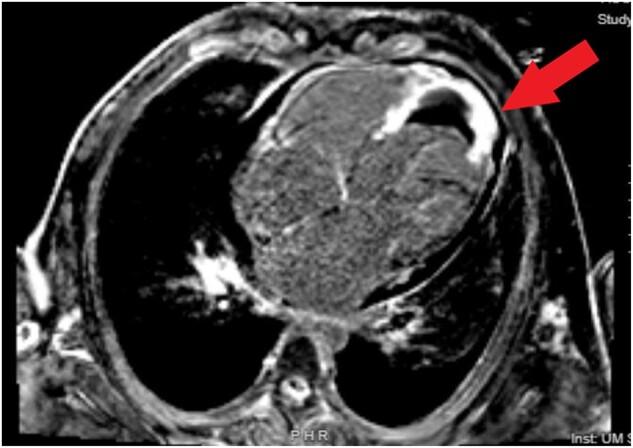

We review the case of a 27-year-old male who presented with acutely decompensated heart failure several months after a motor vehicle accident with chest wall impact from the steering wheel. Coronary angiography demonstrated an occluded left anterior descending artery, and he was found to have a severe ischaemic cardiomyopathy. After multiple hospital and intensive care unit admissions due to multi-organ dysfunction and debility, he was unable to tolerate any guideline-directed medical therapy. He was unable to be listed for heart transplantation due to his co-morbidities, multi-system sequelae of his heart failure, deconditioning, and recent substance use. He was ultimately discharged home with hospice.

我们回顾了一名27岁男性的病例,该患者在机动车事故中胸部受到方向盘撞击数月后出现急性失代偿性心力衰竭。冠状动脉造影显示左前降支动脉闭塞,他被诊断为严重缺血性心肌病。由于多器官功能障碍和虚弱,他多次入住医院和重症监护病房,无法耐受任何指南指导的药物治疗。由于他的合并症、心力衰竭的多系统后遗症、身体机能下降以及近期使用药物,他无法被列入心脏移植名单。他最终在家中接受临终关怀出院。